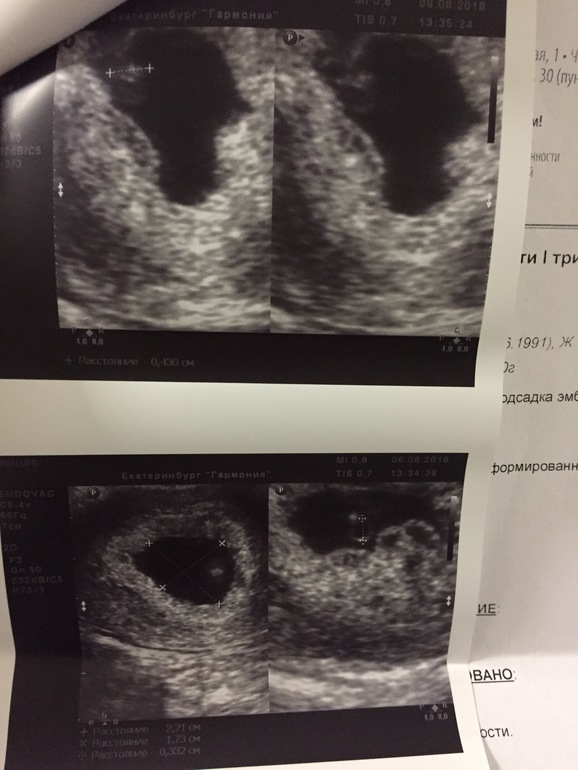

Образуется плацента из хориона — зародышевых оболочек плода. В самом начале беременности ворсины хориона – выросты оболочки — равномерно покрывают всю поверхность плодного яйца, начиная со второго месяца беременности с одной стороны плодного яйца ворсины начинают удлиняться, увеличиваться в размерах и формируют плаценту.

Врач собирает анамнез для уточнения наличия противопоказаний к проведению процедуры. Делает УЗИ для определения срока беременности. Берет анализы мазка на флору, группы крови и резус фактора. На первом приеме гинеколог подробно расскажет о том, как будет проходить медикаментозный аборт, какие ощущения могут быть и какие осложнения могут возникнуть. Для окончательного принятия решения, врач отпускает вас домой на 48 часов подумать.

4.Контроль УЗИ после аборта.